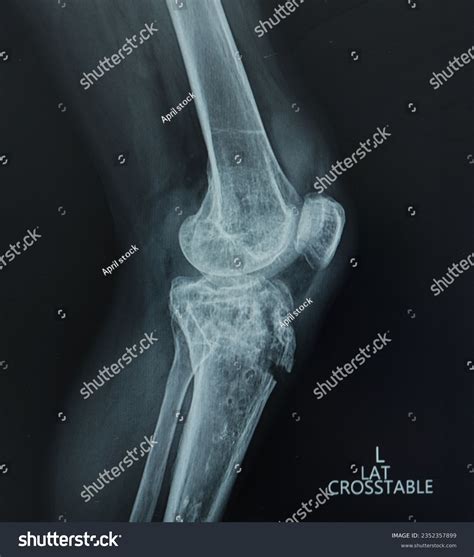

To confirm the diagnosis, medical professionals typically utilize imaging studies. X-rays are the gold standard for visualizing the displaced bone fragment and determining the severity of the fracture. In more complex or comminuted cases, an MRI may be ordered to assess the condition of the surrounding soft tissues, including the patellar tendon and menisci.

Immediate recognition of symptoms is crucial for effective treatment. Patients suffering from a Tibial Tuberosity Avulsion usually experience instantaneous, severe pain directly below the kneecap. The injury is often accompanied by a distinct "popping" sound or sensation at the time of impact.

• Deformity: A visible or palpable gap or bump may be present at the site of the injury.